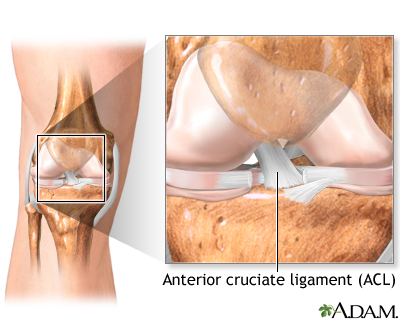

The knee joint is located where the end of the thigh bone (femur) meets the top of the shin bone (tibia).

Four main ligaments connect these two bones:

- Anterior cruciate ligament (ACL) is in the middle of the knee. It prevents the shin bone from sliding out in front of the thigh bone.

- Posterior cruciate ligament (PCL) works with the ACL. It prevents the shin bone from sliding backward under the femur.